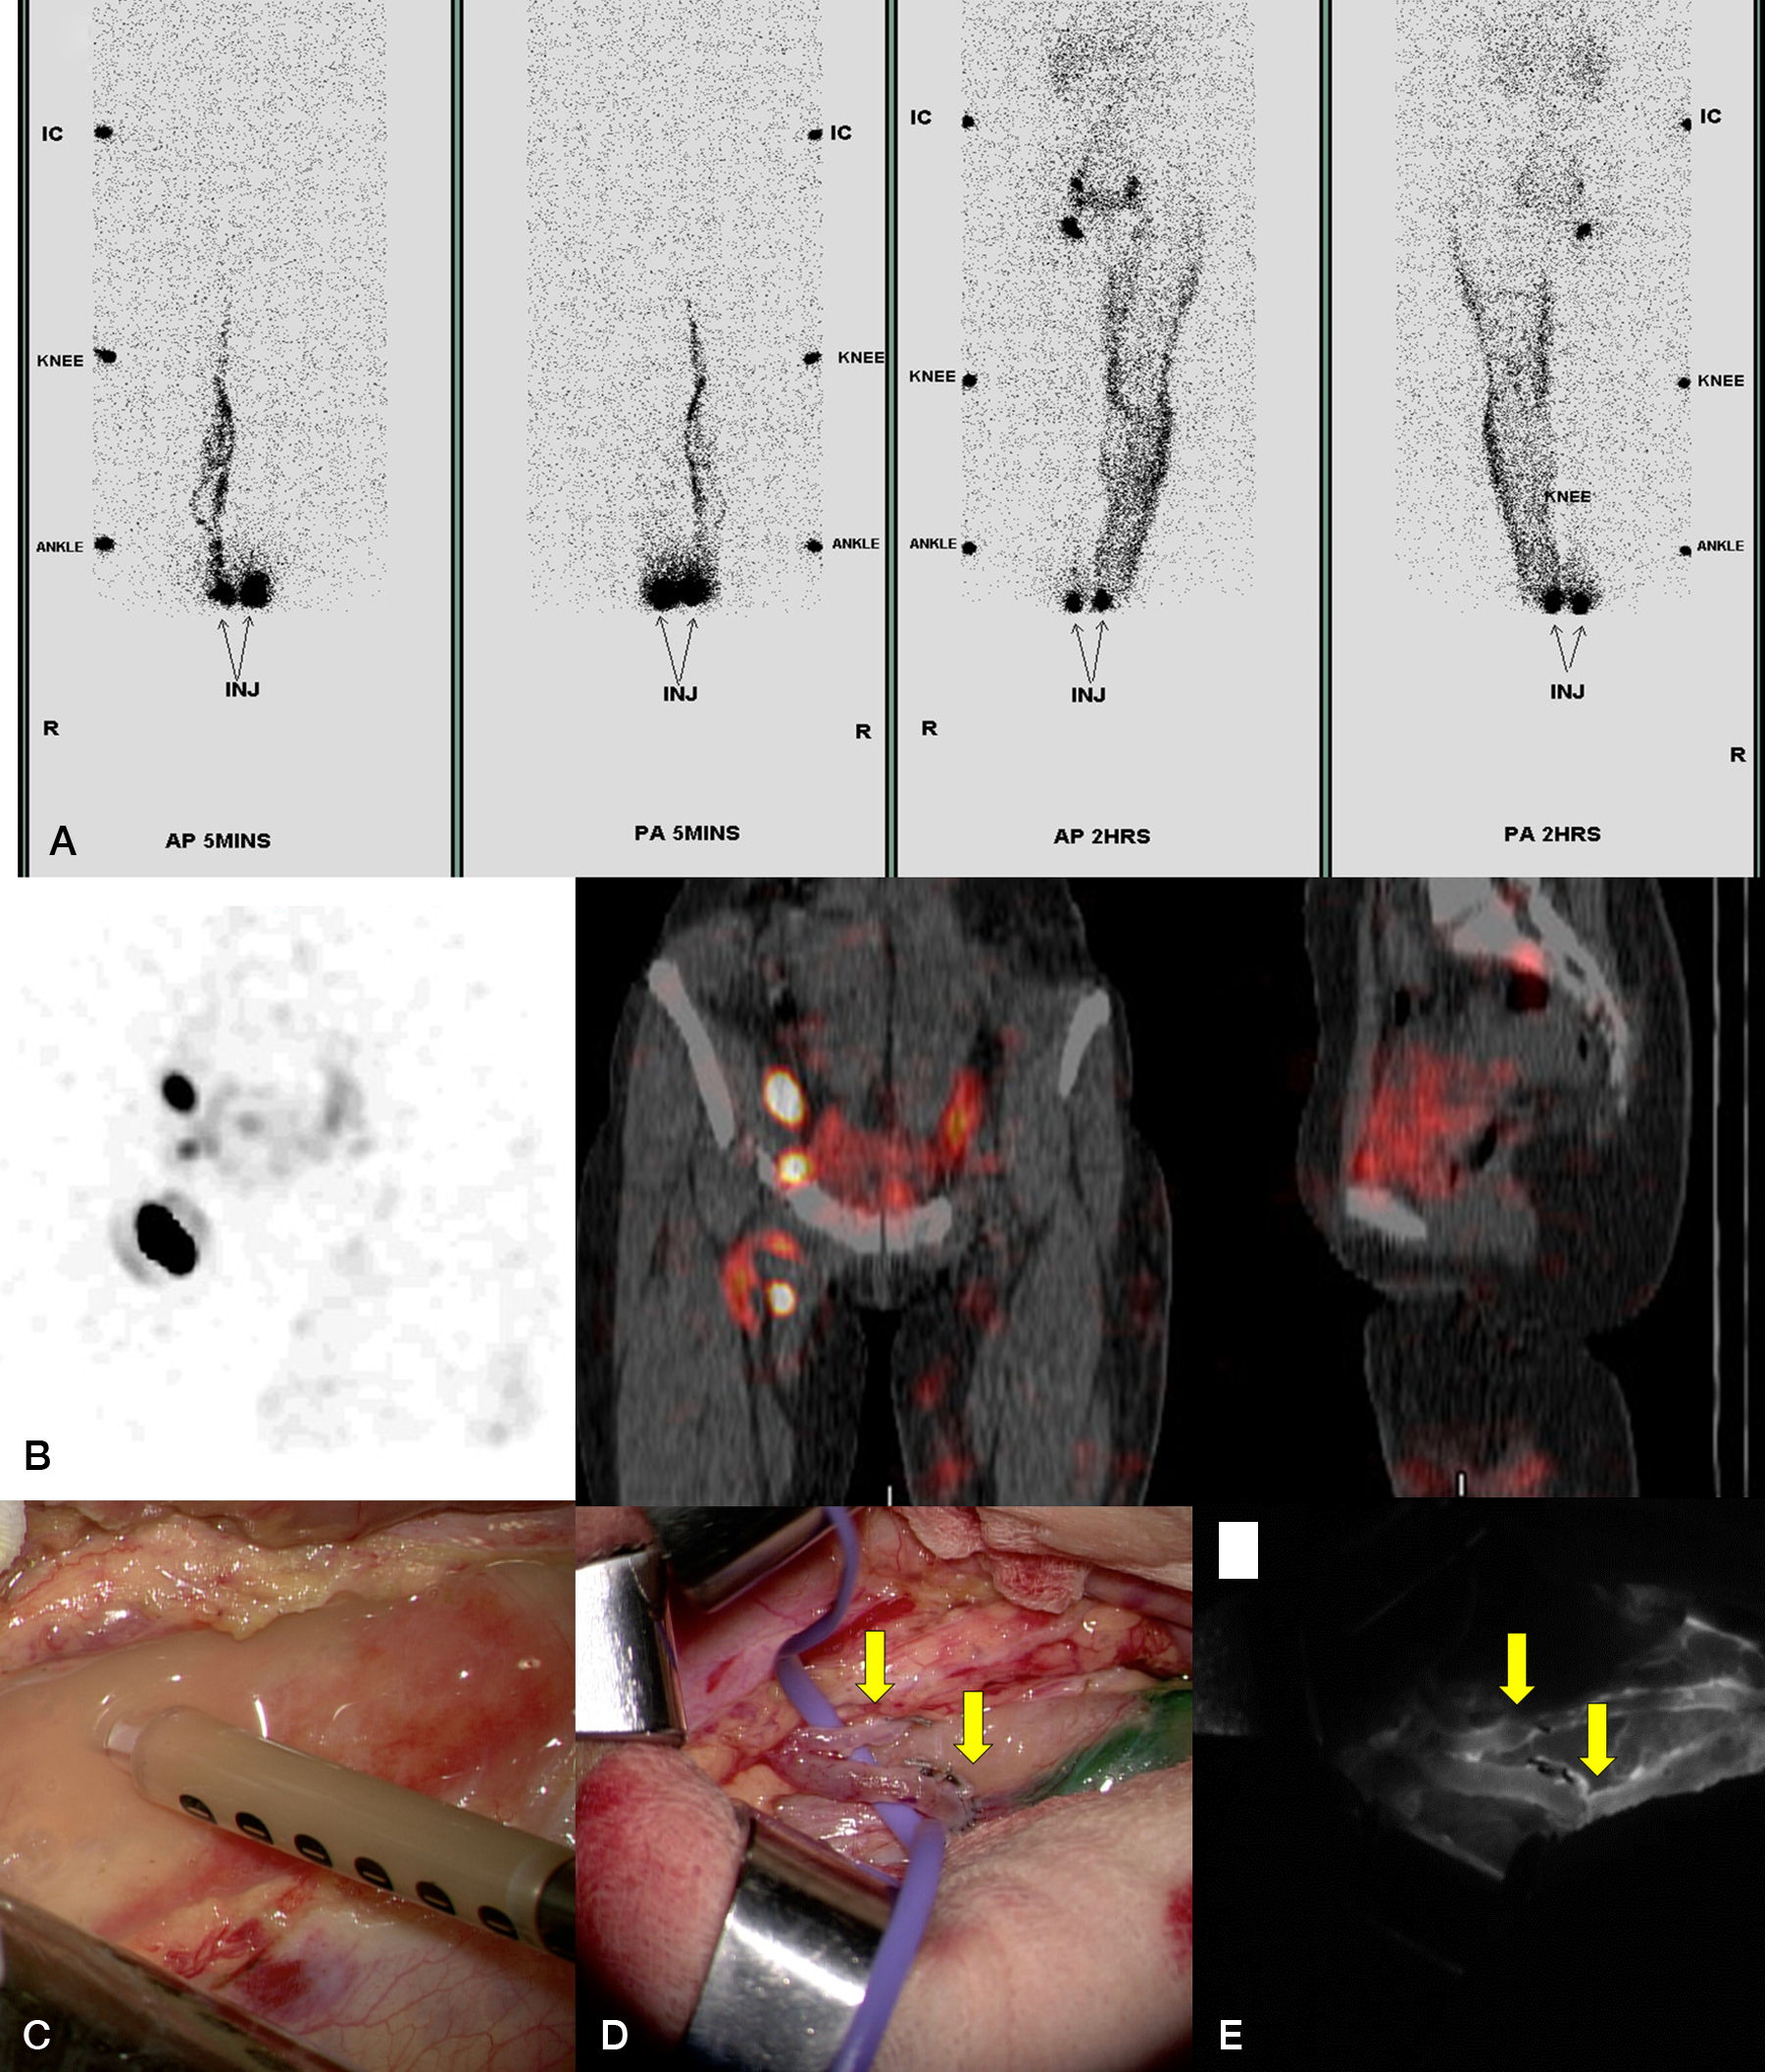

CVB was first described by Chen et al. in 2019 to bypass the intra-abdominal chylous ascites into the venous system. During exploratory laparotomy, the chyle leakage caused by the malformation of lymphatics was identified from the visualization of focal milky exudate by exploration of the retroperitoneum and then confirmed under the microscope. Typically, the location was found to be between the level of the umbilicus and that of the anterior superior iliac spine, around the ureter and internal iliac artery. Bipolar cautery was used to create a hole 4 mm in diameter on the surface of the lymphangiomatosis soft tissue to provide a controlled outlet for chyle. For the recipient vein, either the ovarian vein or branches of the internal iliac vein was utilized for the drainage of chyle. The distal end of the recipient vein was then anastomosed to the lymphangiomatosis outlet in a side-to-end fashion using 8–12 interrupted stitches with 9-0 nylon. The patency was then confirmed with ICG injection at the distal site of lymphangiomatosis ( Fig. 5.3 ).